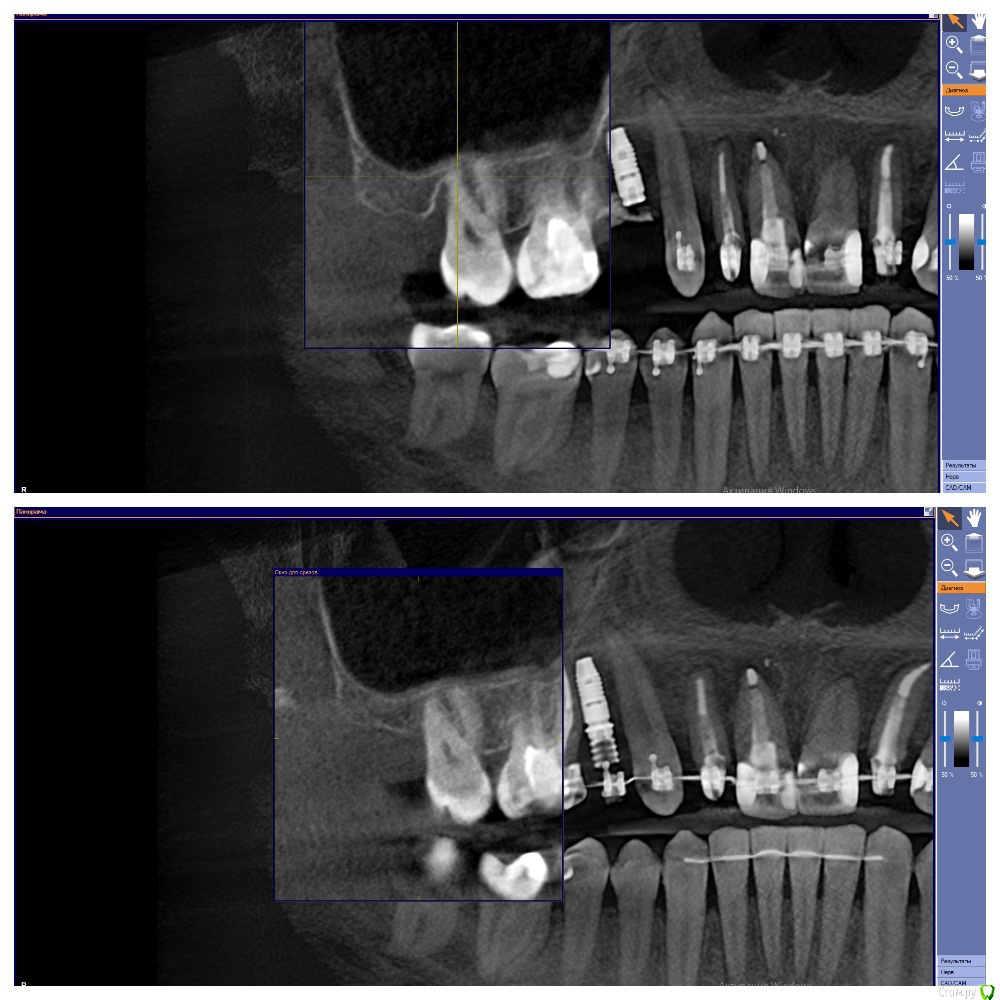

Al..ks Опубликовано 28 мая, 2020 Поделиться Опубликовано 28 мая, 2020 (изменено) Добрый день. Нужен совет. В августе 2019 года, во время установки формирователя десны чистили десневой карман у 17 (грануляции и тд) и подсыпали туда материал какой то, чтоб кость нарастить. А через пол года был план - осмотр и возможно еще подсыпать.К сожалению врач, которая это делала ушла из клиники и на консультацию через полгода пошел уже к другому.Он сделал КТ (зондом не смотрел карман) и сказал , что ничего не надо больше подсыпать, только наблюдать. Меня немного морочит - зуб немного шатается, и полость полностью не заросла костью.Вот фото КТ (сверху было, снизу стало) Изменено 28 мая, 2020 пользователем Al..ks Ссылка на комментарий

Al..ks Опубликовано 5 июня, 2020 Автор Поделиться Опубликовано 5 июня, 2020 Если вы и сами во всем разбираетесь, то зачем спрашиваете совета?, если бы у вас зуб был без перегрузки, то он бы не шатался.По этому снимку вся же предистория не видна (до брекетов - где не понятно как были контакты было: - 16 резорцинформалиновый сильно наклонен, 17, 18. Между ними иногда кровило при чистке ирригатором. 18 заболел перед самой установкой - удалили и в процессе выяснилось - нет костной стенки между ними и когда все зашили и зажило,то остался карман глубиной где-то 11мм. Ну а дальше .... Сейчас (когда его "отключили" от дуги) он шатается уже не так сильно, но по ощущениям чуть сильнее чем "подключенные" к дуге брекетов. Ссылка на комментарий